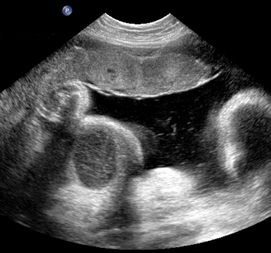

Above. Case 1. 24 3/7 weeks gestation. Sacrococcygeal teratoma. Longitudinal scan of lower spine showing sacrum with associated mixed cystic and solid mass.

Above. Case 1. 24 3/7 weeks gestation. Sacrococcygeal teratoma. An oblique scan through the same area shows both solid and cystic areas as well as calcifications, which are commonly seen in teratomas. The mass appeared completely external.

Above. Case 1. 24 3/7 weeks gestation. Sacrococcygeal teratoma. Similar part of the tumor as above showing cysts of various sizes.

Above. Case 1. 24 3/7 weeks gestation. Sacrococcygeal teratoma. The predominant cyst is large and contains anechoic fluid. No polyhydramnios or evidence for fetal hydrops were noted. Delivery occurred at term. Uneventful resection and repair occurred on day 2 of life.